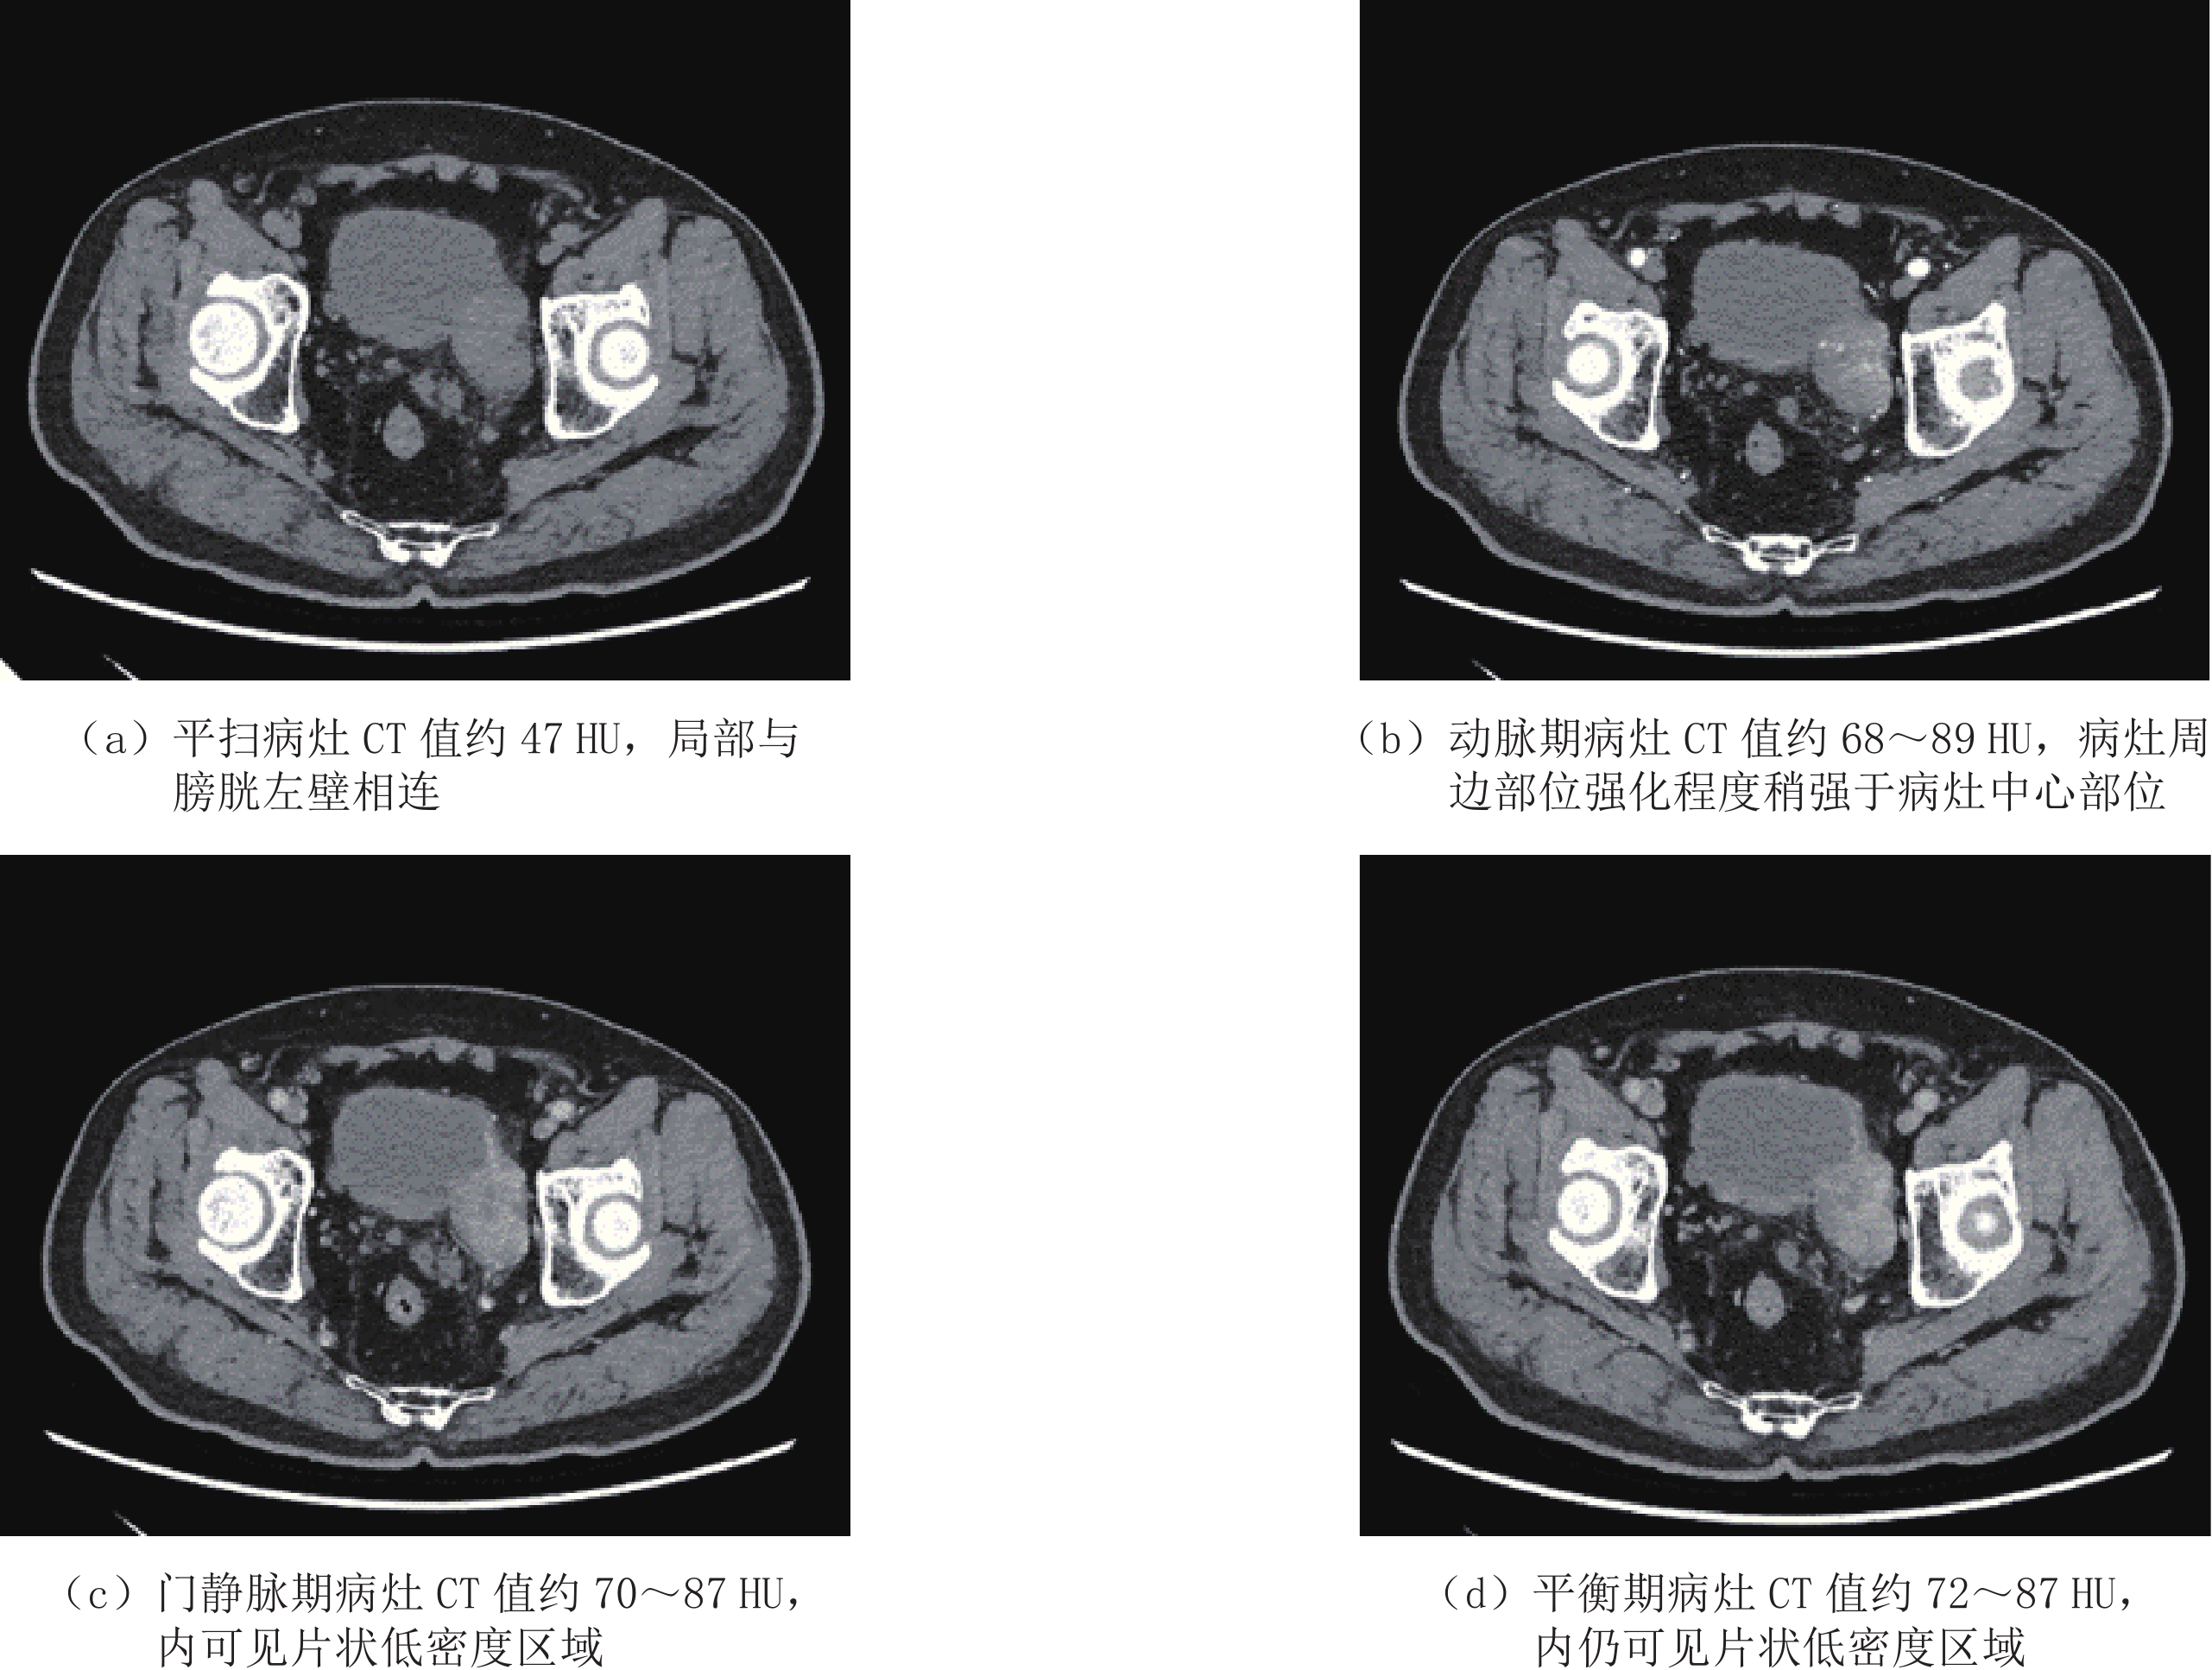

盆腔CT平扫及增强检查(图1)。盆腔左侧可见软组织密度肿块影,形态稍欠规则,密度欠均,边缘可见小结节样钙化,平扫病灶主体CT值约47 HU,边界较清,大小约42 mm×38 mm×35 mm(图1(a)),增强扫描呈不均匀强化,动脉期CT值约89 HU,静脉期及平衡期CT值分别约为87 HU和85 HU。病灶内另可见稍低密度区,平均CT值约24 HU,动脉期及静脉期无明显强化。病变与膀胱左后壁分界欠清,似与膀胱相交通,局部膀胱壁稍厚(图1(b)~图1(d))。膀胱右侧壁可见一小憩室。

膀胱憩室癌CT表现为憩室内软组织密度的结节或肿块,与憩室壁以蒂或广基底相连,病变局部可见钙化,肿块较大时可由于坏死导致病灶密度不均;增强扫描动脉期病灶呈中度强化,静脉期扫描强化程度减低[9]。本例患者的CT及MR检查中,病变区憩室显示不满意,增加了诊断的难度。典型的膀胱憩室癌CT尿路造影(CT urography,CTU)排泄期表现具有特征性,可见憩室内的肿块周围显示造影剂填充,病变处造影剂呈充盈缺损[10]。CT上膀胱憩室癌患者肿瘤宽度和肿瘤与憩室壁之间的接触长度与患者的总生存期密切相关[11]。本例患者可见与膀胱左侧壁分界欠清的肿块,CT增强检查3期肿块强化程度差异小,未见明显的造影剂廓清,且肿块周围未见明显造影剂环绕,需与来源于盆腔内膀胱外并侵及膀胱的肿瘤进行鉴别。本例患者的影像学检查不足之处在于未行CTU检查。